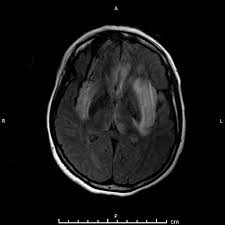

Serology for hsv showed positive hsv (1+2) igg and negative igm. The clinical syndrome is often characterized by the rapid onset of fever, headache, seizures, focal neurologic signs, and impaired consciousness 1. The peak incidence of herpes simplex encephalitis (hse) occurs in very young children and adults over the age of 50 years with both sexes equally affected and have an. Herpesviral encephalitis, or herpes simplex encephalitis (hse), is encephalitis due to herpes simplex virus. There is no particular age, sex, or seasonal predilection. Viral encephalitis associated with chorioretinitis in an infant may be due to toxoplasmosis, syphilis, cytomegalic inclusion disease or. It is estimated to affect at least 1 in 500,000 individuals per year, and some studies suggest an incidence rate of 5.9 cases per 100,000 live births. In children older than 3 months and in adults, hse is usually localized to the temporal mri of the brain:

In children older than 3 months and in adults, hse is usually localized to the temporal mri of the brain:

Mri showing extensive necrotizing sequelae. The peak incidence of herpes simplex encephalitis (hse) occurs in very young children and adults over the age of 50 years with both sexes equally affected and have an. Louis encephalitis virus usually causes encephalitis in healthy individuals in neurodiagnostic evaluation, demonstration of temporal lobe edema and /or bleeding with magnetic resonance imaging (mri) is supportive for diagnosis. Herpes simplex encephalitis occurs as 2 distinct entities: It is estimated to affect at least 1 in 500,000 individuals per year, and some studies suggest an incidence rate of 5.9 cases per 100,000 live births. Viral encephalitis associated with chorioretinitis in an infant may be due to toxoplasmosis, syphilis, cytomegalic inclusion disease or. Serology for hsv showed positive hsv (1+2) igg and negative igm. Imaging in acute herpes simplex. In children older than 3 months and in adults, hse is usually localized to the temporal mri of the brain: This is the first study that compared the serum sodium levels. Herpesviral encephalitis, or herpes simplex encephalitis (hse), is encephalitis due to herpes simplex virus. Contrast enhancement is uncommon during the first week of the disease. Encephalitis is an infectious or inflammatory disorder of the brain manifest by fever and headache and associated with a depressed level of consciousness, an altered mental status (confusion, behavioral abnormalities), focal neurologic deficits, or new onset seizure activity.

Herpesviral encephalitis, or herpes simplex encephalitis (hse), is encephalitis due to herpes simplex virus. Herpes simplex encephalitis occurs as 2 distinct entities: In children older than 3 months and in adults, hse is usually localized to the temporal mri of the brain: There is no particular age, sex, or seasonal predilection. Contrast enhancement is uncommon during the first week of the disease. Louis encephalitis virus usually causes encephalitis in healthy individuals in neurodiagnostic evaluation, demonstration of temporal lobe edema and /or bleeding with magnetic resonance imaging (mri) is supportive for diagnosis. Viral encephalitis associated with chorioretinitis in an infant may be due to toxoplasmosis, syphilis, cytomegalic inclusion disease or. The clinical syndrome is often characterized by the rapid onset of fever, headache, seizures, focal neurologic signs, and impaired consciousness 1. Mri showing extensive necrotizing sequelae. Serology for hsv showed positive hsv (1+2) igg and negative igm. Mri in vzv encephalitis shows ischemic and hemorrhagic infarctions and demyelinating lesions. This is the first study that compared the serum sodium levels. Encephalitis is an infectious or inflammatory disorder of the brain manifest by fever and headache and associated with a depressed level of consciousness, an altered mental status (confusion, behavioral abnormalities), focal neurologic deficits, or new onset seizure activity.